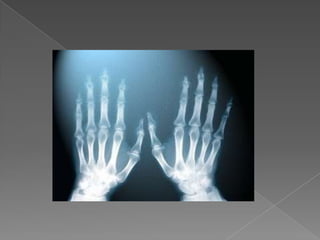

ПРИЛОЖЕНИЕ В МЕДИЦИНАТАРентгеновителъчи се използват в медицината от 1895 и сапървият вид радиация, с помощта на която е наблюдаванавътрешността на човешкототяло. Рентгеновителъчипреминаватпрезтъканите на тялото и същопритежаватсвойството да потъмняватфотографскифилм, когатопреминатпрезтях.Различнитеоргани и тъкани на човешкототялопоглъщатрентгеновителъчи в различна степен: например костите и други образования, съдържащикалций, гипоглъщатпо-силно от мекитетъкани, на което се основаваизползването на рентгеновителъчи в медицината за наблюдение на вътрешнитеорганиначовека – кости, бели дробове и др. Изследваната част от тялото се осветява с рентгеновителъчи, които частично се поглъщат от нея, преминалителъчипопадатвърхуфотографскифилм.

ПРИЛОЖЕНИЕ В МЕДИЦИНАТАРентгеновителъчисе използват в медицината от 1895 и сапървият вид радиация, с помощта на която е наблюдаванавътрешността на човешкототяло. Рентгеновителъчипреминаватпрезтъканите на тялото и същопритежаватсвойството да потъмняватфотографскифилм, когатопреминатпрезтях.Различнитеоргани и тъкани на човешкототялопоглъщатрентгеновителъчи в различна степен: например костите и други образования, съдържащикалций, гипоглъщатпо-силно от мекитетъкани, на което се основаваизползването на рентгеновителъчи в медицината за наблюдение на вътрешнитеорганиначовека – кости, бели дробове и др. Изследваната част от тялото се осветява с рентгеновителъчи, които частично се поглъщат от нея, преминалителъчипопадатвърхуфотографскифилм.